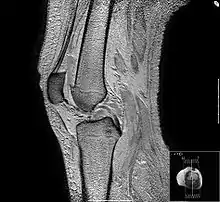

- L'antenne genou : il s'agit d'une antenne émettrice-réceptrice ou réceptrice simple. Il s'agit d'une antenne modulaire de 22 cm de diamètre (peut varier). Elle est adaptée à l'exploration du genou, mais aussi du pied et de la cheville.

- les articulations et les structures adjacentes (hanches, genoux, ménisques, ligaments croisés), notamment chez les sportifs ;